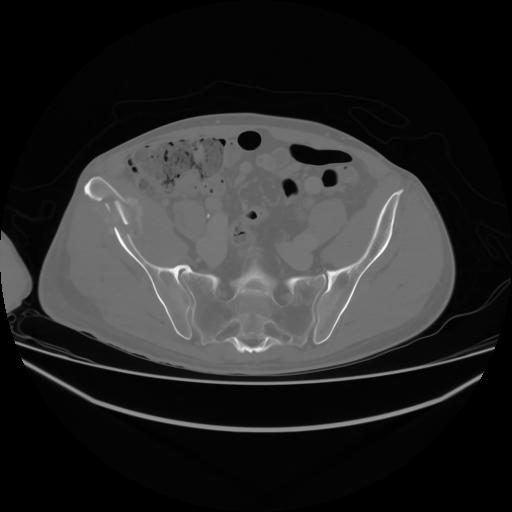

4 CUERPO,CE,Axial,3.0,CUERPO,,